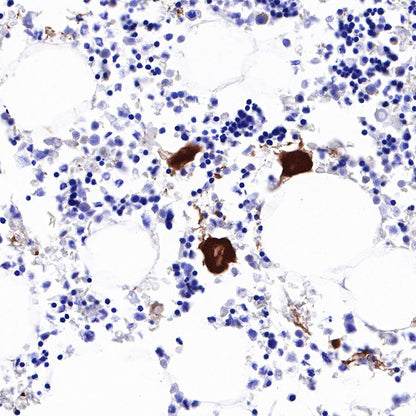

Immunohistochemistry

IHC shows positive staining in paraffin-embedded human spleen. Anti-CD226 antibody was used at 1/1000 dilution, followed by a HRP Polymer for Mouse & Rabbit IgG (ready to use). Counterstained with hematoxylin. Heat mediated antigen retrieval with Tris/EDTA buffer pH9.0 was performed before commencing with IHC staining protocol.